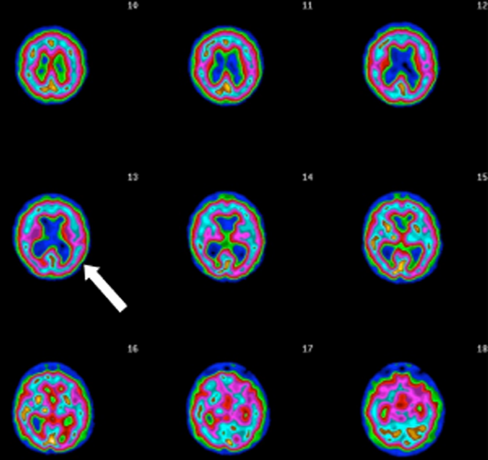

TRANSAXIAL SLICES

Slices 12 and 13 show inverted lobster pattern,

associated with ventricular enlargement.

TEMPORAL LOBE DYSFUNCTION

Severe left temporal lobe hypoperfusion shown (arrow) consistent with epilepsy.

HYPERFRONTALITY ACTIVE SCAN

Severe hyperfrontality (arrow), a pattern consistent

with OCD.

HYPOFRONTALITY SURFACE SCAN

Low prefrontal cortex perfusion

(holes at top of image)